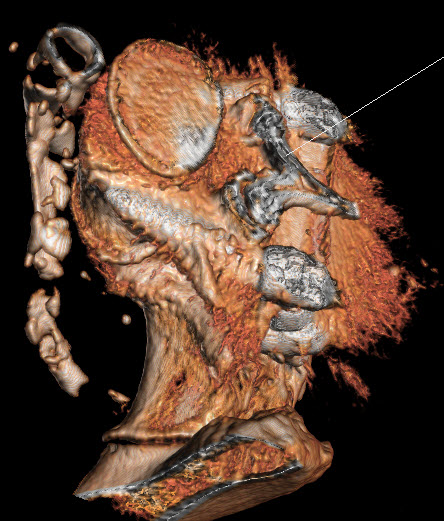

17-JANUARY-2021  HUDA AHMAD DAASAN  57 YEARS  UNACCEPTABLE UPPER SCREWS LOCATION AFTER FIXATION DONE 3 DAYS AGO.

The patient power of the lower limbs improved, but she is telling that the right gastrocnemius muscle is tight. Control CT-scan of the constructs performed the evening of 16-January-2021 showed unacceptable both upper screws at the level of L5. The sacral screws are acceptable. It was decided to explore the wound redirect the upper screws.

The left upper screw far-lateral.

The right upper screw far lateral and above the pedicle.

The upper screws are far lateral.

X-ray reconstruction using ORS Visual program

Post correction performed 18-January-2021